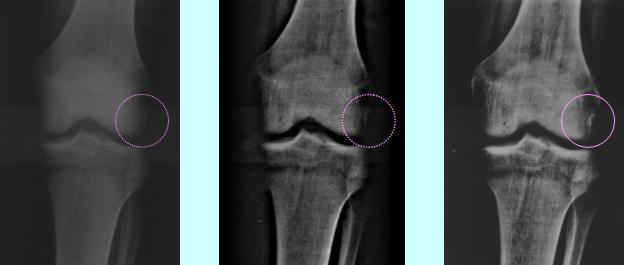

(3)画像診断支援

レントゲン、CT、MRI、超音波、PET等の医用画像に結像した病巣を強調するためには、従来の線形的な

フィルタでは難しい場合があります。

弊社では、病巣毎に特有な

画像特徴量に反応する選択的な非線形フィルタを、ファジィ技術を用いて連続性を保ちながら作用

させることにより、各種の病巣を自然に浮き立たせ、診断を支援いたします。

原画像                   線形フィルタ                 非線形フィルタ